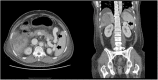

Man with tarry stools